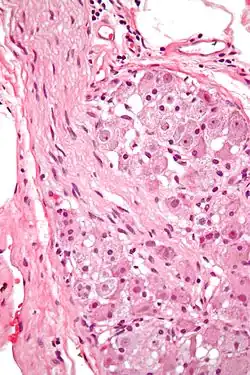

![]() Various forms of nerve cells.